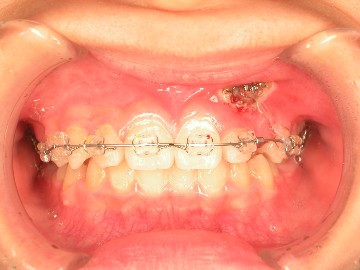

患者陳小妹妹(治療時僅9歲),於本院接受齒顎矯正治療,經數位X光(圖二)診斷,左側乳犬齒之上尚有埋伏的恆牙犬齒為假牙,使用口內攝影(圖二)與病患解釋,建議患者處理方式如下:

圖一 |